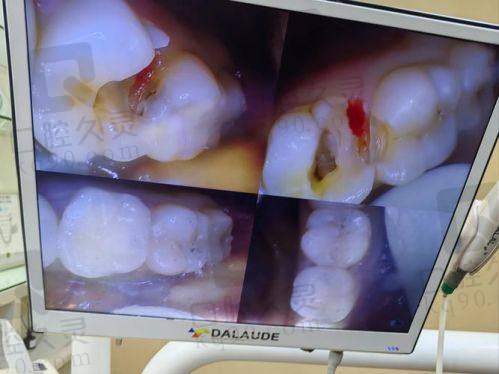

河源拜博口腔引进了精良的口腔诊疗设备,比如口腔CT、数字化牙片机等。这些设备可以更正确地诊断孩子牙齿的问题,为治疗提供更科学的依据。同时,医院也采用了精良的补牙技术和材料,确保治疗的成效和质量。